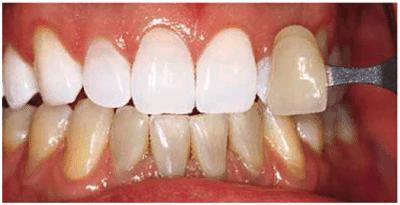

either on an individual tooth or on all teeth (Figures 16-1A, and 16-1B). There are many causes and

Figure 16-1A: An otherwise attractive smile is marred by discolored teeth.

Figure 16-1B: After tooth lightening, the smile is much more pleasing.